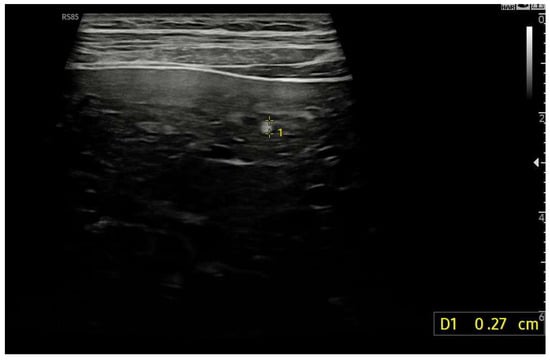

Figure 16.

Diffusely dense and heterogeneous echostructure due to the presence of multiple and diffuse hyperechoic areas consistent with FNH-like nodules.

Figure 17.

Hyperechoic oval lesion of 2.7 mm, compatible with a FNH-like nodule, identified using a high-frequency linear probe.